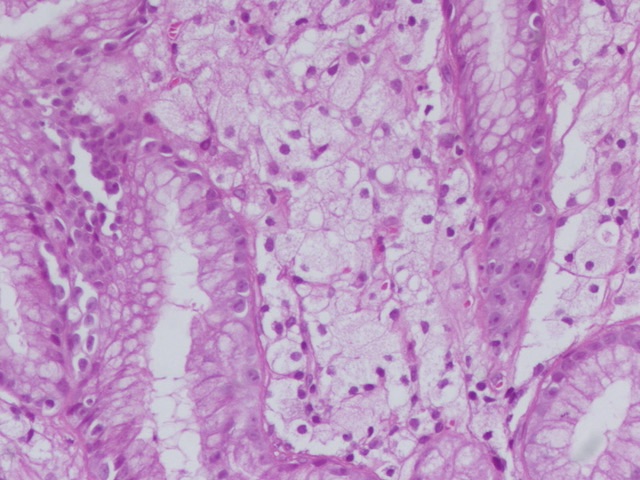

How not to share this #beautyinB9 #GIPath #Pathresidents #PathOutPic Gastric xanthomas appear as pale or yellowish plaques or nodules, typically less than 3 mm in size, located in the gastric mucosa. They are often found in clusters, more frequently along the lesser curvature

2

12

43